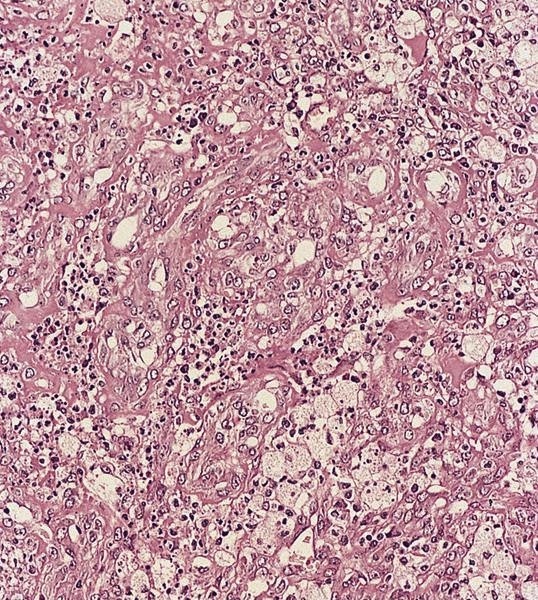

Microscopic (histologic) description

- Focal nodal effacement by multiple coalescing intranodal clusters of small blood vessels, lined by epithelioid endothelial cells with pale cytoplasm

- May have focal nuclear atypia

- Interstitium contains abundant eosinophilic to amphophilic, amorphous or granular material containing aggregates of bacteria (highlighted by Warthin-Starry stain)

- Also neutrophils

Microscopic (histologic) images

AFIP images

- Post vaccination bacille Calmette-Guerin infection occurs in 1% of infants, although swelling usually subsides (Braz J Med Biol Res 2004;37:697)BACILLARY ANGIOMATOSIS Left: Proliferated blood vessels are separated by abundant eosinophilic, vaguely fibrillary material. Some neutrophils are also seen. Right: Barely canalized blood vessels separated by eosinophilic interstitial materials in the absence of neutrophils.